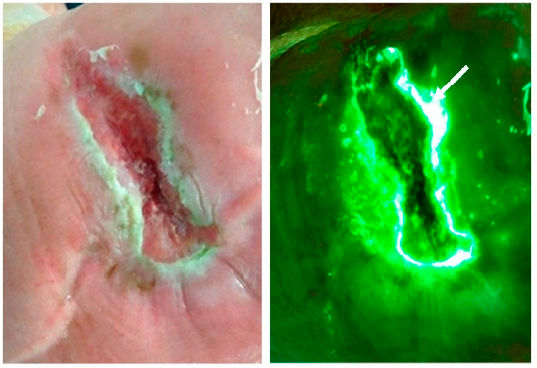

Rapid diagnosis of Pseudomonas aeruginosa in wounds with point-of-care fluorescence imaging

Raizman, R et al. Diagnostics 2021